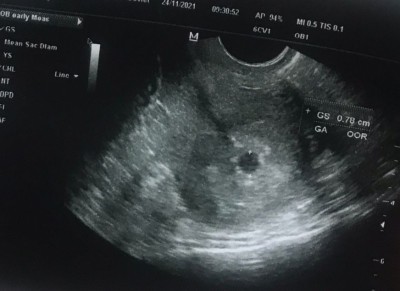

5+4 haftalik gebeyim 2 gun önce keseyi gördük ama sıvı da vardı bebeğe zarar verirmi